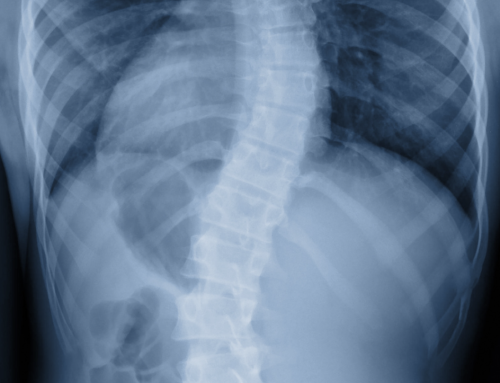

Scoliosis is a common condition of the spinal column and I see it often in my practice. It is defined by a curvature in the spinal column, generally from side to side. It is a complicated three-dimensional defect, on an X-ray, viewed from the back, the spinal column of an individual with scoliosis may look more like an “S” or a “C” than a straight line. The quantity of curvature can vary from a hardly noticable few degrees to nearly > 70-80 degrees. Scoliosis is frequently idiopathic (i.e. no-one understands what actually triggers it), however there are other types as well, that are less typical. When it come to the most typical type of scoliosis, teen idiopathic scoliosis, the cause may be attributed to a variety of elements, including genetics. This condition impacts roughly 7 million individuals in the United States.

Patients were given interviews to identify the severity of their low pain in the back and analyzed according to a standardized spinal column test, which involved the taking of x-rays, and measurement of angles such as Cobb and lumbar lordosis.